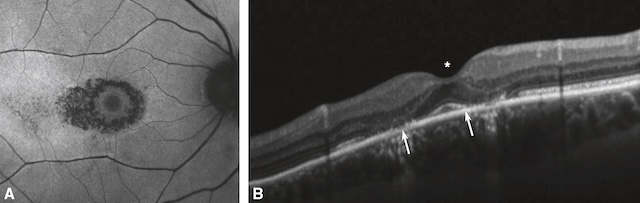

Moins fréquents que les membranes épimaculaires, les trous maculaires correspondent à une perte de la continuité du tissu neurosensoriel dans la région maculaire par écartement des berges fovéolaires. Ils sont le plus souvent d’apparition rapide ou rapidement progressive avec 155baisse d’acuité visuelle et scotome central. Des métamorphopsies sont souvent associées. Là encore, l’examen clé reste l’OCT (fig. 7.6 et fig. 7.7) qui permet de confirmer le diagnostic, de mesurer la taille du trou et de poser l’indication chirurgicale (vitrectomie).

A. Aspect de trou maculaire visible au fond d’œil sous la forme d’une lésion orange foncé, arrondie, à bords nets. B. Écartement des berges maculaires (flèches), responsable de la perte de continuité de la rétine neurosensorielle. Noter le décollement du vitré postérieur en regard (astérisque).

Vue en deux parties montrant un trou maculaire. Partie A : Photographie couleur du fond d’œil d’un patient présentant une perte de continuité au niveau de la région maculaire. L’image révèle une zone centrale légèrement plus sombre dans la région fovéale, caractéristique d’un trou maculaire. Partie B : Image en tomographie en cohérence optique (OCT) transversale de la rétine montrant un trou maculaire complet. L’image met en évidence une interruption nette du tissu neurosensoriel au centre de la fovéa. On observe un écartement des berges fovéolaires (indiqué par deux flèches blanches) et une séparation du vitré postérieur (indiquée par un astérisque), ainsi qu’une hyperréflectivité intrarétinienne autour de la zone du trou.

Image en deux parties montrant un trou maculaire observé par tomographie en cohérence optique (OCT). Partie A, à gauche : image infrarouge en réflectance de la rétine avec superposition de deux lignes de balayage vertes encadrant un trou rond et bien défini au niveau de la macula. Partie B, à droite : coupe transversale OCT de la rétine correspondant à la zone balisée, montrant une perte nette de la continuité du tissu neurosensoriel fovéolaire. On observe un écartement symétrique des bords rétiniens avec présence de kystes intrarétiniens bilatéraux.